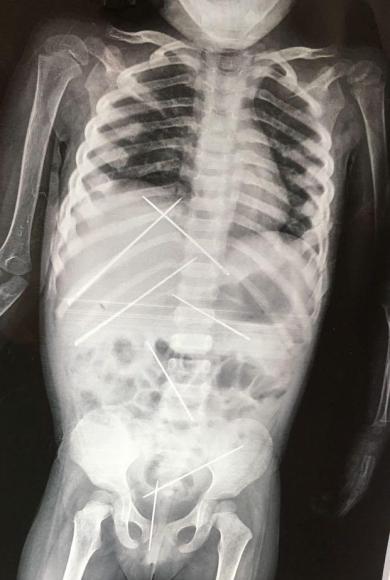

Τετάρτη, 19 Ιουλίου, 2017Φρίκη: Γεμάτο βελόνες το κορμάκι 3χρονης από μαύρη μαγεία

Τραγική κατάληξη για ένα 4χρονο κοριτσάκι είχαν τα βασανιστήρια στα οποία το υπέβαλλαν οι γονείς του.